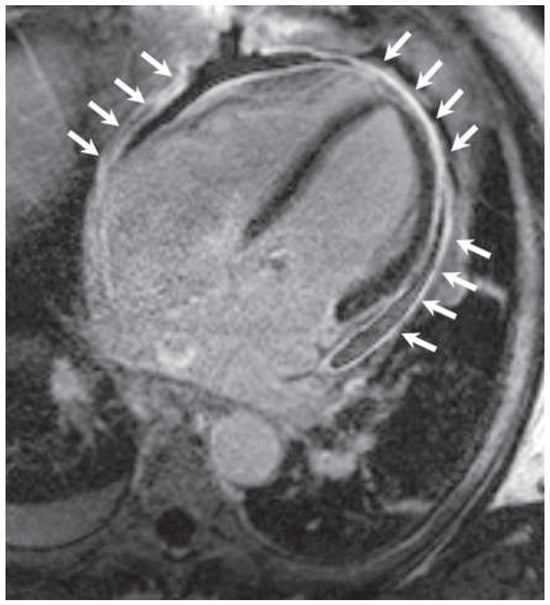

Kussmaul's Sign in Effusive Constrictive Pericarditis

by Mattia Cattaneo, Stefano Muzzarelli, Francesco Faletra, Alessandra Pia Porretta, Francesco Siclari and Augusto Gallino

Cardiovasc. Med. 2015, 18(1), 32; https://doi.org/10.4414/cvm.2015.00296 - 21 Jan 2015

A 67-year old man with mitral valve prolapse and moderate regurgitation was admitted because of dyspnoea, bilateral ankle swelling and hypotension. Close inspection of the jugular veins identified Kussmaul’s sign, a typical increase in the central venous pressure during inspiration (fig. 1; arrows) [...] Read more.

A 67-year old man with mitral valve prolapse and moderate regurgitation was admitted because of dyspnoea, bilateral ankle swelling and hypotension. Close inspection of the jugular veins identified Kussmaul’s sign, a typical increase in the central venous pressure during inspiration (fig. 1; arrows) [...]